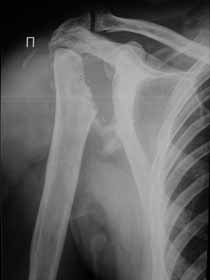

Не усмотрел в анамнезе "ноябре 2009 - травма с потерей сознания. В феврале 2010 г - первый рентген правого плечевого сутава - перелом анатомитеской шейки".

Поэтому желательно выставить все рентгенологические и данные МРТ для сравнения со снимками из статьи.

Думаю, коллеги будут не против увидеть рентген.

Извиняюсь, что-то фотографии сразу не прошли. сейчас исправимся.

Все таки мы решили, что это посттравматичкский аваскулярный некроз. Принято волевое решение выполнить гемиартропластику. На операции: выраженная гипертрофия стенок субакромиальной бурсы. Она была раздута, на операции произведено ее вскрытие, эвакуировано 450 мл суставной геморрагической жидкости. По возможности бурса максимально иссечена, хотели промыть спиртовым расствором хлоргексидина, но побоялись. Вращ манжета - остатки ее найдены в задних отделах сустава, прикрепленные к большому бугорку. малого бугорка и сухожилия подлопаточной мышцы найдено на месте не было. нашли конечно, что-то похожее на сухожилие подлопаточной мышцы и пришили к кости, но я до конца не уверен. полость была дренирована. Сегодня 3 сут после операции - сустав отечен, из дренажа за сутки выделяется около 250 мл геморрагической жидкости. Однако это уже меньше чем в первые дни. Получает НПВС: нимулид по 1т 2 раза и диклофенак 1,0 в/м в сут. Вне зависимости от исхода, постараюсь рассказать об этом в следующих сообщениях. У кого есть мысли по этому, буду очень рад.